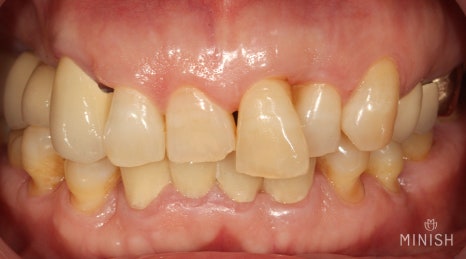

평택엄마의 아랫니는 틀어지고 벌어져 예쁘지 않을 뿐 아니라 틈새로 음식물이 튀고 침이 새는 문제가 있었다고 합니다. 넉넉치 못한 형편 속에서도 불편함 때문에 성급하게 크라운 브릿지 치료를 결정했죠.

가지런해 보이는 아랫니

그 속은 어떨까요 ?

과거 크라운 브릿지 치료 속 상태